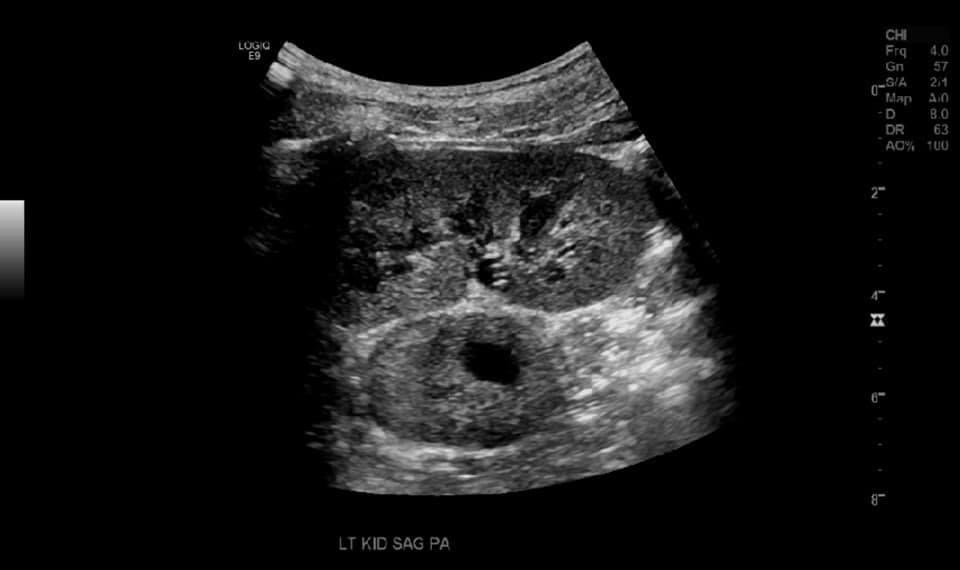

An adolescent patient presented for ultrasound with a history of tachycardia and diaphoresis. On ultrasound examination a heterogenous mass was seen medial to the left renal pelvis which was determined to be extra adrenal pheochromocytoma after further investigation.

CT and MRI are the imaging of choice. On ultrasound, pheochromocytomas have a variable appearance ranging from solid (75% in one case series) to mixed cystic and solid to cystic. [3] IN our case the lesion was located near the left renal hilum and had cystic and solid components and some vascularity on color doppler.